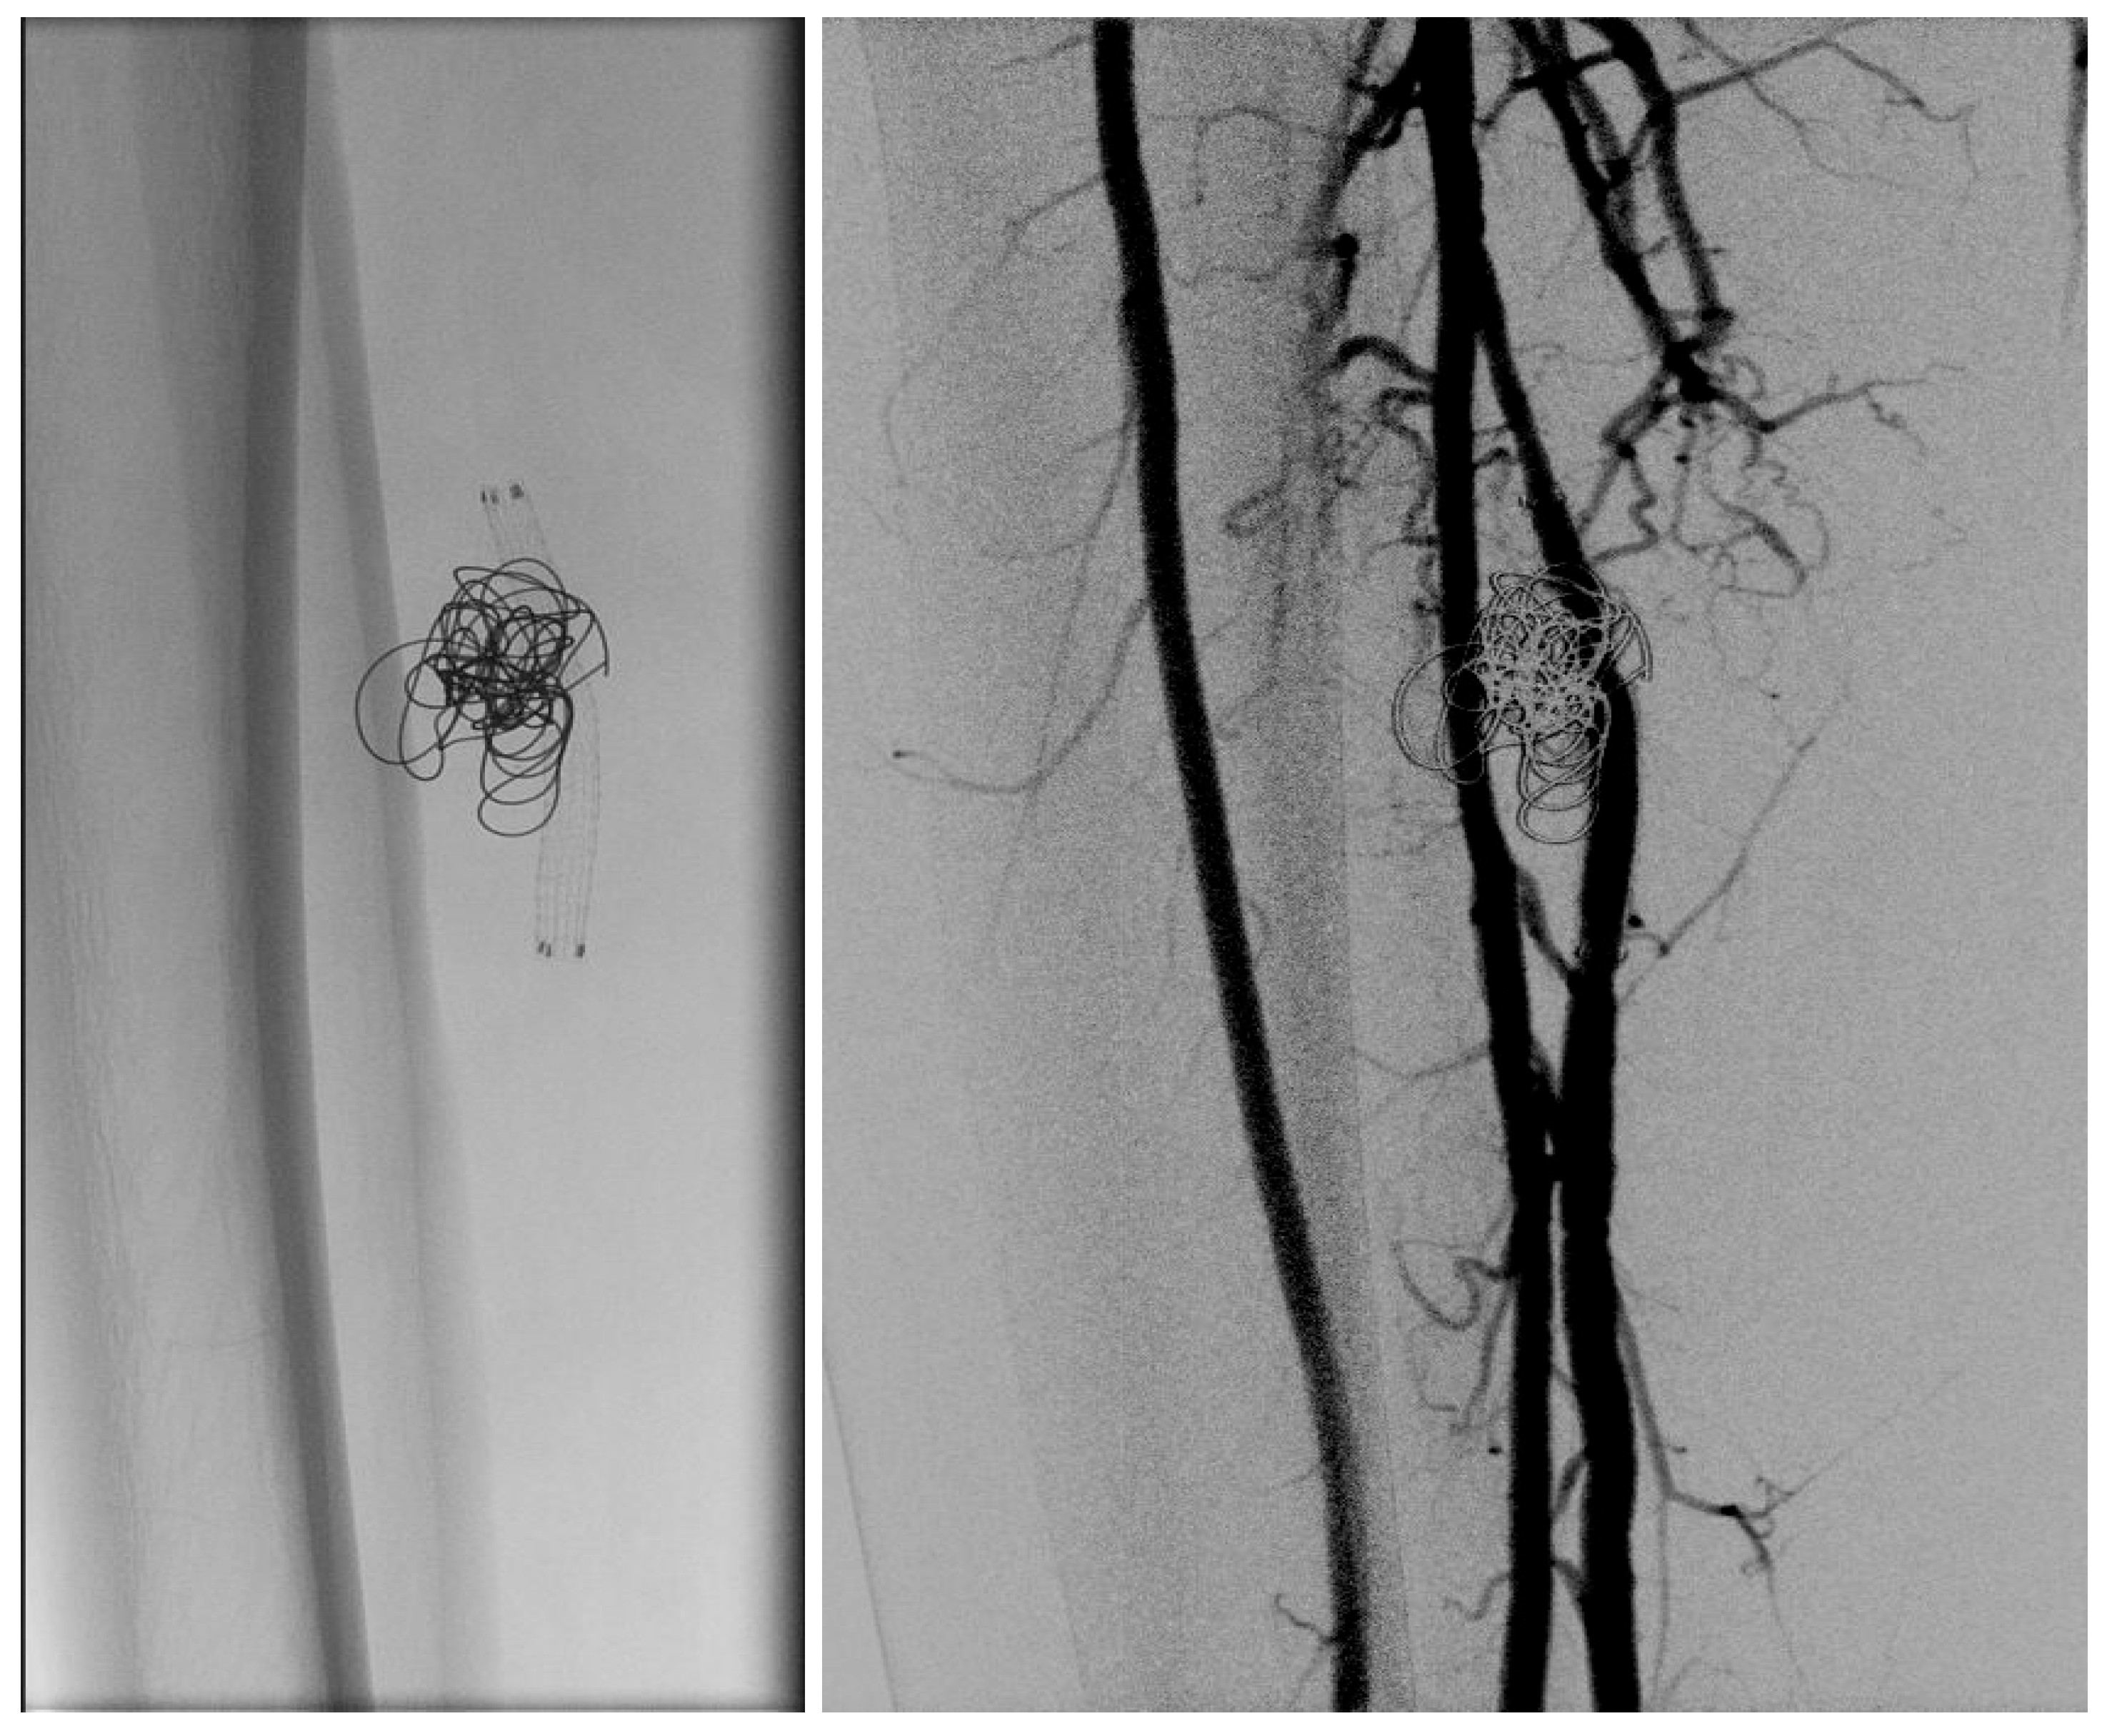

- Yamamoto Y. Et al. Endovascular coil embolization of a large tibioperoneal trunk pseudoaneurysm. Journal of Vascular Surgery Cases and Innovative Techniques 2020; Volume 6 number 3.

- Micari, A. et al. Tibioperoneal trunk pseudoaneurysm coil embolization 2010 Catheter Cardiovasc Interv vol.75 (2) 276-8.

- Miura, T. et al. Iatrogenic peroneal artery pseudoaneurysm treated by transluminal coil embolization 2013 Cardiovasc Interv Ther vol. 28 (1) 128-30.